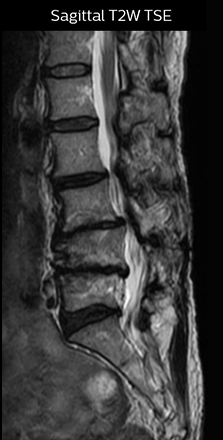

“Before NerveVIEW, diagnosis by MRI alone was sometimes difficult, unless there was a strong suspicion based on clinical symptoms,” says Shoji Yabuki, MD, DMSc, Orthopedic surgeon at Fukushima Medical University School of Medicine. “This is why we routinely perform selective lumbosacral radiculography (nerve root block) and x-ray in such cases. However, radiculography can only depict nerves as far as the contrast agent reaches. When a nerve is distorted by compression, the contrast agent will not pass through this compressed area, preventing us from evaluating the full nerve compression.”

The key concept in MR neurography, Dr. Yabuki stresses, is the ability to directly visualize spinal nerves, versus inferring the presence of pathology indirectly. “Before NerveVIEW, we estimated compression of the nerve by looking for the presence or absence of fat signal on other MR images,” he says.

“For example, in sagittal images, when the presence of fat is observed in the intervertebral foramen, it suggests that there is a margin around the nerve. Similarly, the absence of fat indicates that the nerve is being compressed. So, we used to deduce nerve compression indirectly. With NerveVIEW, however, we can observe the condition of the nerves directly, regardless of the presence or absence of fat. We always prefer such direct observation of anatomy over having to make an inference about it.”